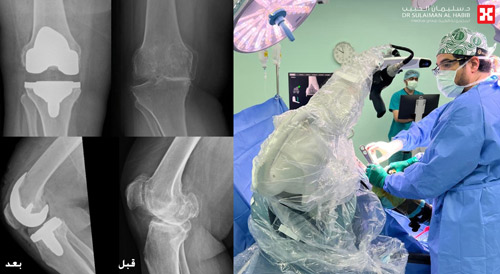

عملية متقدمة لاستبدال مفصل الركبة لسيدة بمجمع الدكتور سليمان الحبيب الطبي بالعليا

أعادت عملية متقدمة لاستبدال الركبة، بمساعدة تقنية الروبوت الجراحي، بمجمع الدكتور سليمان الحبيب الطبي بالعليا، القدرة على الحركة لمريضة تبلغ من العمر «60» عاماً، ذكر ذلك د. يوسف خوجة استشاري جرحة العظام واستبدال المفاصل والإصابات الرياضية، رئيس الفريق الطبي المعالج. وقال د. يوسف إن المريضة